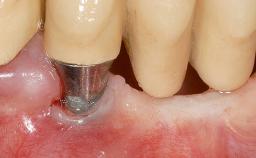

Treatment of Soft-Tissue Fenestration in the Esthetic Zone

This case demonstrates that a connective-tissue graft in combination with a coronally positioned graft is an effective method of treating cases with peri-implant mucositis and an abutment-level sinus abscess. A 42-year-old man presented with a swelling adjacent to an implant crown at site 21. The swelling had been present for approximately three weeks and was constrained to the buccal and palatal gingival aspects of the implant. A discharge was noted on finger pressure, with localized gingival recession present on the mid- and distolabial aspects of the crown.